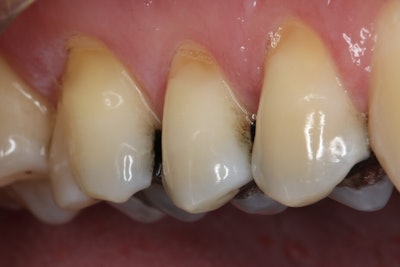

After administering local anesthesia and placing a rubber dam, the existing amalgam restoration was removed and the fracture of the buccal cusp was addressed through controlled reduction. One challenge encountered during the treatment process was the presence of deep caries.

To address this issue, the clinician followed the Fusayama concept of selective caries removal, a well-established protocol from the 1980s. Caries Detector dye guided the removal of infected caries, and the tooth was prepared for a Katana Zirconia One crown, following a 1-mm reduction protocol (Figure 2).

Figure 2.